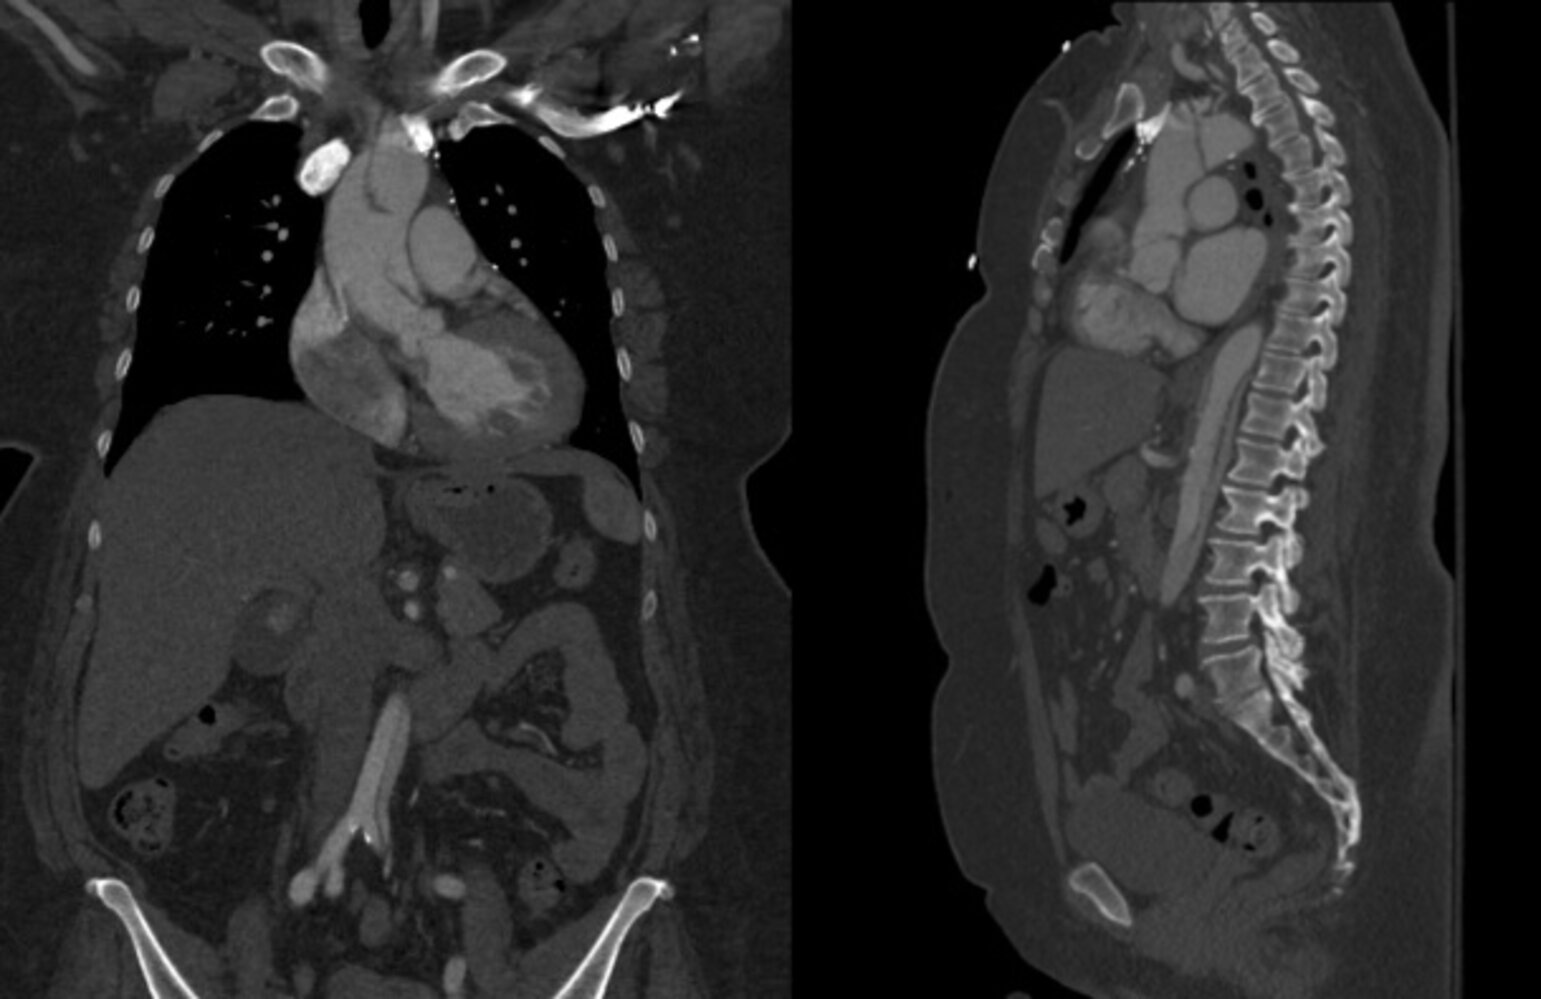

Aortic dissection [9][10][11]

• Sudden onset of severe, sharp tearing chest or abdominal pain that radiates to the back

• Hypertension or hypotension

• Asymmetrical blood pressure, pulse deficit

• New diastolic murmur

• Symptoms of myocardial ischemia

• Syncope, neurological symptoms

• Labs: Elevated D-dimer

• ECG: nonspecific ST-segment changes

• CXR: widening of the aorta

• CTA chest, abdomen, and pelvis: intimal flap with false lumen

• TEE: proximal aortic dissection, tamponade, aortic regurgitation

• See β€œAcute management checklist for aortic dissection.”

Thoracic aortic aneurysm

• Feeling of pressure in the chest

• Thoracic back pain

• Features of mediastinal compression or obstruction (e.g., difficulty swallowing, hoarseness)

• If ruptured: severe chest pain, possible loss of consciousness

• Chest x-ray: abnormal aortic contour, widened mediastinum, tracheal deviation

• CTA chest: dilation of the aorta, possible mural thrombus, dissection, perforation, or rupture

• See β€œAcute management checklist for thoracic aortic aneurysm.”